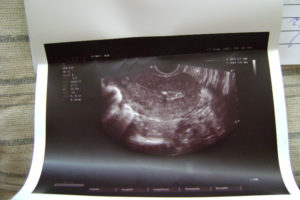

С такими признаками нужно срочно обращаться в клинику. Гинеколог назначит после осмотра ультразвуковое исследование, в ходе которого будет видно внутри осталась плацента или нет. Чтобы устранить последствия, проводится чистка под общим обезболиванием.

5 – 7 дней по окончании родовой деятельности выпадают сгустки крови. Затем они принимают мажущий характер и совсем исчезают. Если спустя 2 – 3 недели изменений не наблюдается, кровь продолжает вытекать, возможно, образовался полип. Когда плацента полностью не вышла после родов, УЗИ показывает увеличенную в размерах матку. Поэтому обильные выделения должны насторожить.

- Ультразвуковое исследование.

Если у вас продолжается обильное кровотечение в течение нескольких дней или недель после родов, вас направят на УЗИ чтобы выявить, не остались ли фрагменты плаценты в матке. Если подозрения подтвердятся, вас направят в больницу для хирургического удаления остатков плаценты из полости матки. Она проводится под анестезией и сопровождается введением антибиотиков.

Чистка матки проводится после родов, если в ней остались части плаценты или скопились сгустки крови. Обнаружить остатки можно на плановом ультразвуковом исследовании, которое проводят после родов.

Отличительной чертой данного заболевания является трудность в его диагностике, потому что начальная стадия приходится на послеродовые кровотечения, характерные для этого периода. Главной причиной полипов считается аборт или выскабливание в анамнезе. Обнаружить плацентарный полип можно только с помощью ультразвукового исследования.